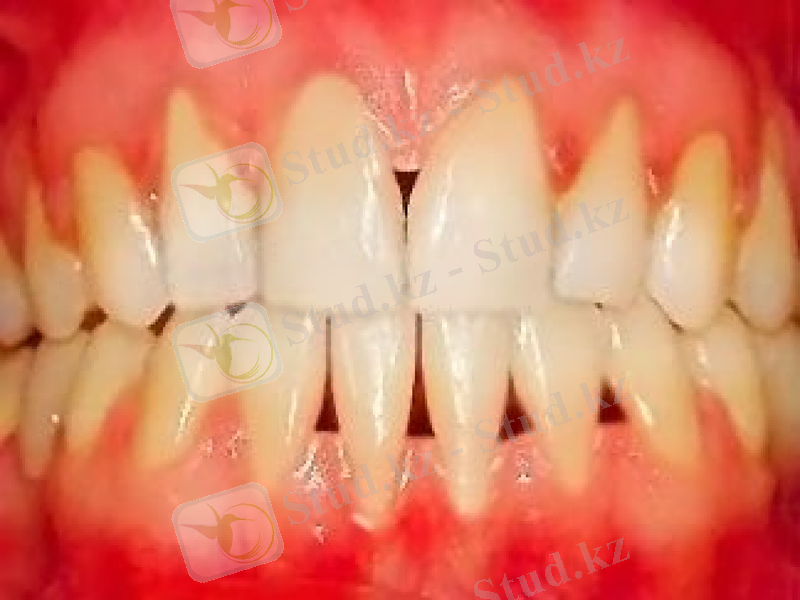

Пародонтоздың жеңіл түрі

Шағымы: жоқ, қызылиекте қышу сезімі және кейбір кезде ыңғайсыздық сезімі

Сырттай қарап тексеру: қызылиек жиегі бозарған, тіс беткейіне тығыз орналасқан, тістер мойындарының бір қалыпты жалаңаштануы, тіс қақтары болмайды немесе шамалы анықталады.

Зондылау: тіс-қызылиек байланысы бұзылмаған, қанағыштық жоқ.

Шиллер-Писарев сынамасы: теріс